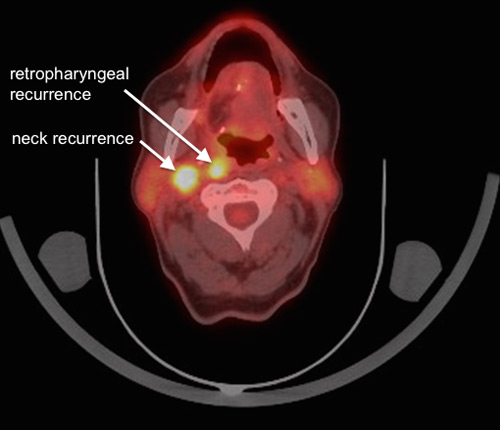

Figure 3

The same follow-up 18F-FDG-PET/CT scan showing the fused 18F-FDG-PET part with the CT part. There is no evidence for local recurrence at the reconstruction site however there are two highly suspicious lymph nodes in level IIb ipsilateral and retropharyngeal.

After all there is no consensus of the perfect time for baseline and follow-up imaging. At our institution first imaging will be done 10 weeks after treatment. After that follow-up imaging is based on the previous findings. Since locoregional recurrence is often seen during the first two years after initial treatment the authors feel there is a legitimate reason for another subsequent scan, e.g., after 12, and 24 months. 18F-FDG-PET/CT is shown to be more accurate than conventional follow-up imaging alone regarding the detection rate of recurrences (fig. 2, and 3) [68]. Any additional imaging modalities should be performed on clinical signs. Suspicious lymph nodes can best be evaluated with USgFNAC.